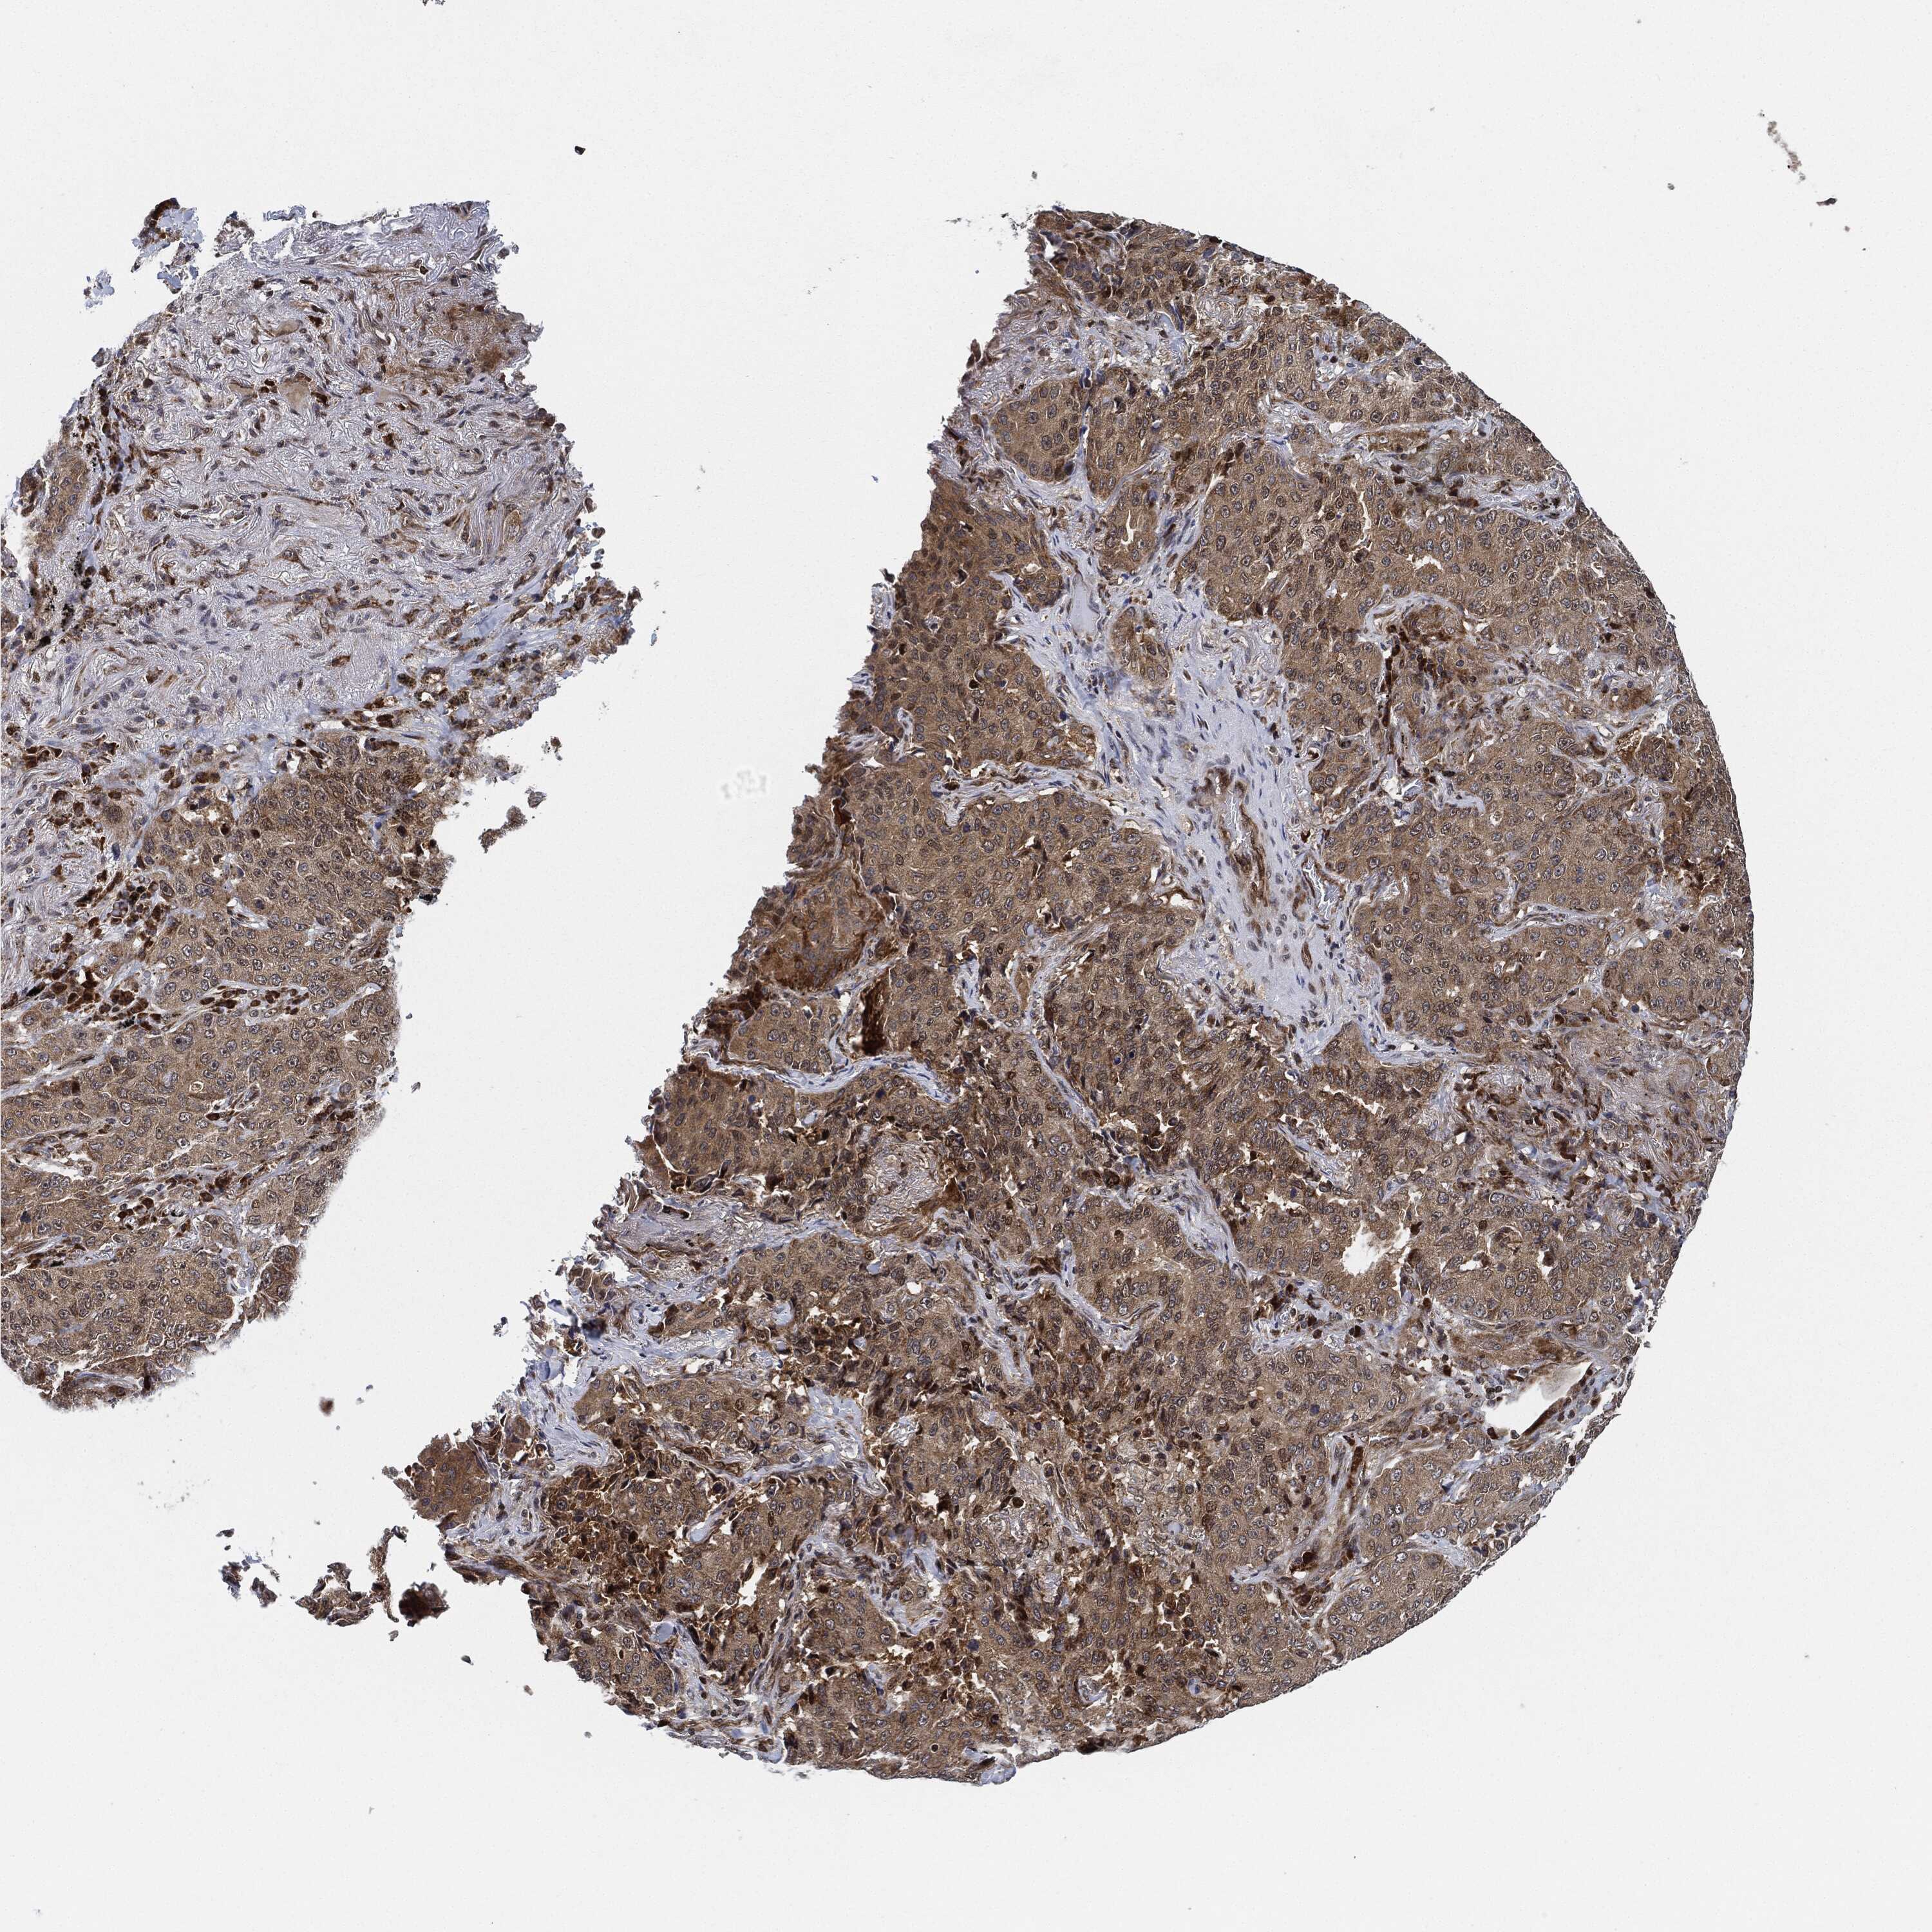

LUNG SQUAMOUS CELL CARCINOMA (TCGA) - Interactive survival scatter ploti

The Survival Scatter plot shows the clinical status (i.e. dead or alive) for all individuals in the patient cohort, based on the same data that underlies the corresponding Kaplan-Meier plots. Patients that are alive at last time for follow-up are shown in blue and patients who have died during the study are shown in red.

The x-axis shows the expression levels (FPKM) of the investigated gene in the tumor tissue at the time of diagnosis. The y-axis shows the follow-up time after diagnosis (years). Both axes are complimented with kernel density curves demonstrating the data density over the axes. The top density plot shows the expression levels (FPKM) distribution among dead (red) and alive patients (blue). The right density plot shows the data density of the survived years of dead patients with high and low expression levels respectively, stratified using the cutoff indicated by the vertical dashed line through the Survival Scatter plot. This cutoff is automatically defined based on the FPKM cutoff that minimizes the p-score. The cutoff can be changed by dragging the vertical line or by entering a cutoff value in the square labeled "Current cut-off".

Under the Survival Scatter plot the p-score landscape (black curve; left axis) is shown together with dead median separation (red curve; right axis). Dead median separation is the difference in median mRNA expression between patients who have died with high and low expression, respectively. It is calculated as follows: median FPKM expression of dead patients with high expression - median FPKM expression of dead patients with low expression. This is intended to aid the user in visually exploring custom cutoffs and the associated p-scores and dead median separation.

Individual patient data is displayed and can be filtered by clicking on one or more of the category buttons on the top of the page. Categories describing expression level and patient information include: high, low, alive, dead, female, male and tumor stages. The scale of the x-axis can be toggled between linear and log-scale by clicking on the "x log" button. Mouse-over function shows TCGA ID, patient information and mRNA expression (FPKM) for each patient.

& Survival analysisi

Kaplan-Meier plots summarize results from analysis of correlation between mRNA expression level and patient survival. Patients were divided based on level of expression into one of the two groups "low" (under cut off) or "high" (over cut off). X-axis shows time for survival (years) and y-axis shows the probability of survival, where 1.0 corresponds to 100 percent.

RNASEL is not prognostic in Lung Squamous Cell Carcinoma (TCGA)

Best expression cut offi

Based on the FPKM value of each gene, patients were classified into two groups and association between prognosis (survival) and gene expression (FPKM) was examined. The best expression cut-off refers the FPKM value that yields maximal difference with regard to survival between the two groups at the lowest log-rank P-value. Best expression cut-off was selected based on survival analysis .

When clicking on this number, the vertical dashed line indicating cut-off, the interactive survival plot, and the Kaplan-Meier curve will be adjusted to show results based on the best expression cut-off.

: 6.84

P scorei

Log-rank P value for Kaplan-Meier plot showing results from analysis of correlation between mRNA expression level and patient survival.

N/A

TCGA RNA samplesi

RNA-seq data is reported as average FPKM (number Fragments Per Kilobase of exon per Million reads), generated by the The Cancer Genome Atlas (TCGA) .

Normal distribution across the dataset is visualized with box plots, shown as median and 25th and 75th percentiles. Points are displayed as outliers if they are above or below 1.5 times the interquartile range. FPKM values of the individual samples are presented next to the box plot.

Average pTPM 5.6

Number of samples 489